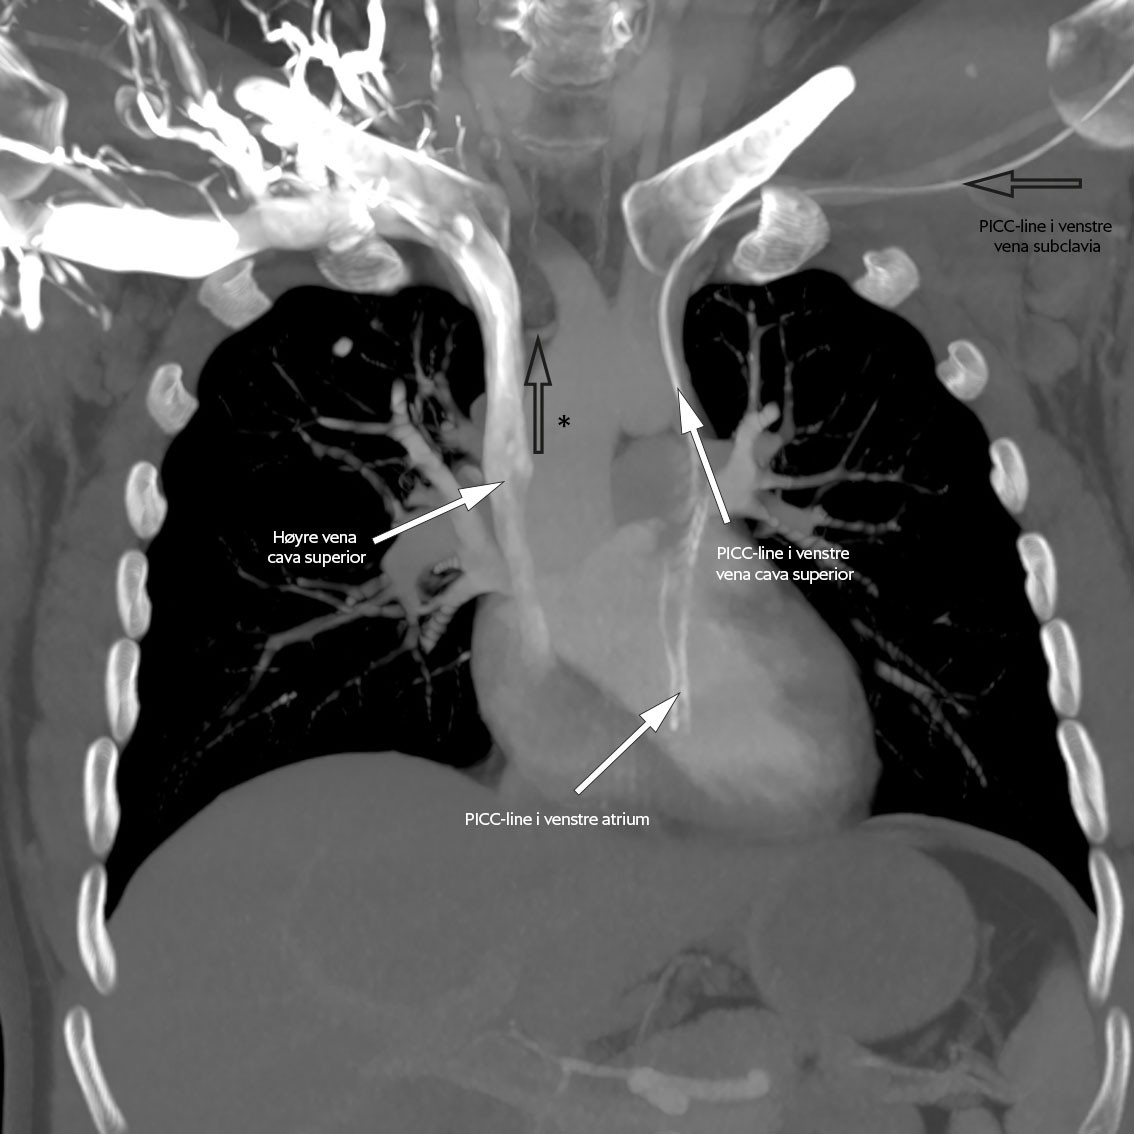

To dager senere sluttet kateteret å fungere, og pasienten fikk et nytt tilsvarende kateter via venstre overekstremitet. Prosedyren var ukomplisert, men kontroll-røntgen toraks viste unormalt leie av kateteret på venstre side av sternum (figur 2). CT toraks med intravenøs kontrast samme kveld viste at kateteret lå i en persisterende venstre vena cava superior, se figur 3a og figur 3b. Grunnet kontrastartefakter på bildene kunne man ikke da si sikkert om denne venen munnet ut i venstre eller høyre hjertehalvdel. Det gikk lett å aspirere blod og å injisere saltvann, og man tolket det som at kateteret fungerte normalt. Pasienten reiste hjem samme kveld i god form.

Ved regranskning av CT toraks tatt ved første innleggelse på universitetssykehus så man at pasienten hadde en persisterende venstre v. cava superior. Det ble nå bekreftet at denne munnet ut i venstre atrium.

Hos 90 % av tilfellene med persisterende venstre v. cava superior drenerer denne til høyre atrium via sinus coronarius. Disse er gjerne asymptomatiske og oppdages tilfeldig ved bildediagnostikk, sentralvenøs kateterisering eller kirurgi (11). De resterende 8–10 % drenerer direkte til venstre atrium via anomalier i sinus coronarius og skaper en høyre-til-venstre-shunt. Disse er assosiert med hjerneabscesser og tromboemboliske hendelser (12).

Pasientens venstresidige perifert innlagte sentralvenøse kateter ble ikke tatt i bruk og etter hvert fjernet. Videre diagnostikk de neste fire ukene bestod i transøsofageal ekkokardiografi, som viste et stort kar som munnet inn i venstre atrium, forenlig med persisterende venstre v. cava superior. Det ble gjort «bobletest» med boblekontrast fra begge overekstremiteter. Ved injeksjon i høyre albuevene var det ingen overgang av kontrast til venstre atrium. Ved injeksjon i venstre albuevene gikk all kontrast til venstre atrium. Dette indikerte tett atrieseptum. I tillegg viste undersøkelsen tett ventrikkelseptum.

Man hadde nå utelukket de tre vanligste årsakene til høyre-til-venstre-shunt: Patent foramen ovale, atrieseptumdefekt og ventrikkelseptumdefekt (19). Funnet bekreftet også at den persisterende venstre v. cava superior drenerte direkte til venstre atrium. Det var ingen tegn til endokarditt. Det ble gjort CT toraks med angiografi for ytterligere kartlegging. Revmatologisk utredning med CT-angiografi av resten av kroppen var uten patologiske funn. På grunn av oppvekst av munnhulebakterier ble det gjort et nytt kjevekirurgisk tilsyn, som var upåfallende.